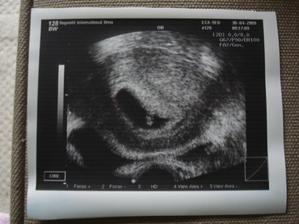

24.4.2009 prni UVZ, je tam gestacny vacek a miminko se zacinajici srdecni akci ma 2-3mm, jeste to nejde poradne zmerit

30.4.2009 druhy UVZ, mame prvni fotecku, srdicko krasne blikalo a mame 6,4mm

16.9.2009 další poradna, opět vše v pořadku akorát prcek sedí na zadečku a tlačí maminku hlavičkou do žeber ;) tak doufame, že se co nejdřív otočí